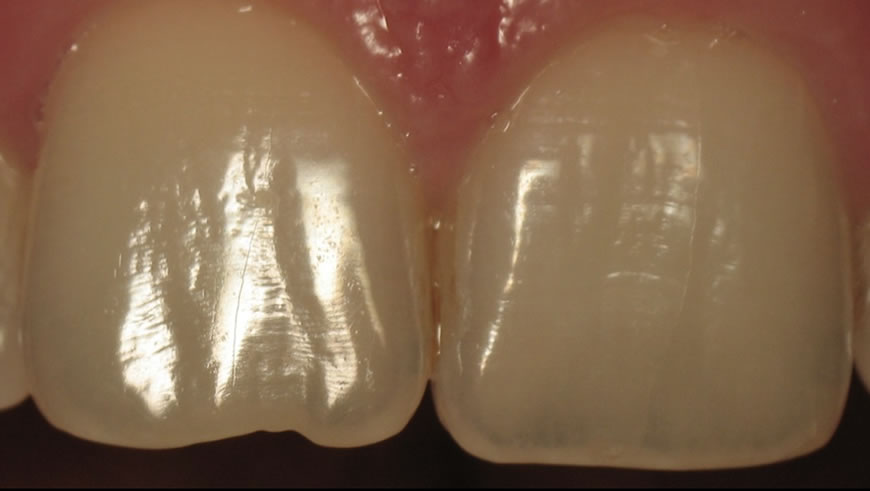

– L’effet nacré : effet surtout visible chez les sujets jeunes dont les surfaces dentaires donnent un effet de brillance métallique.

– La macro et microgéographie ou état de surface : elle va conditionner la réflexion du flux lumineux réfléchi, très marquée chez le sujet jeune, elle diminue avec l’âge et l’usure abrasive et érosive.

– Les caractérisations (taches, fissures, sillons) qui va permettre l’intégration de la restauration au milieu des dents naturelles. Elles sont naturelles (tache de fluorose) ou acquises (fêlures colorées, infiltrations) et de profondeur variable.